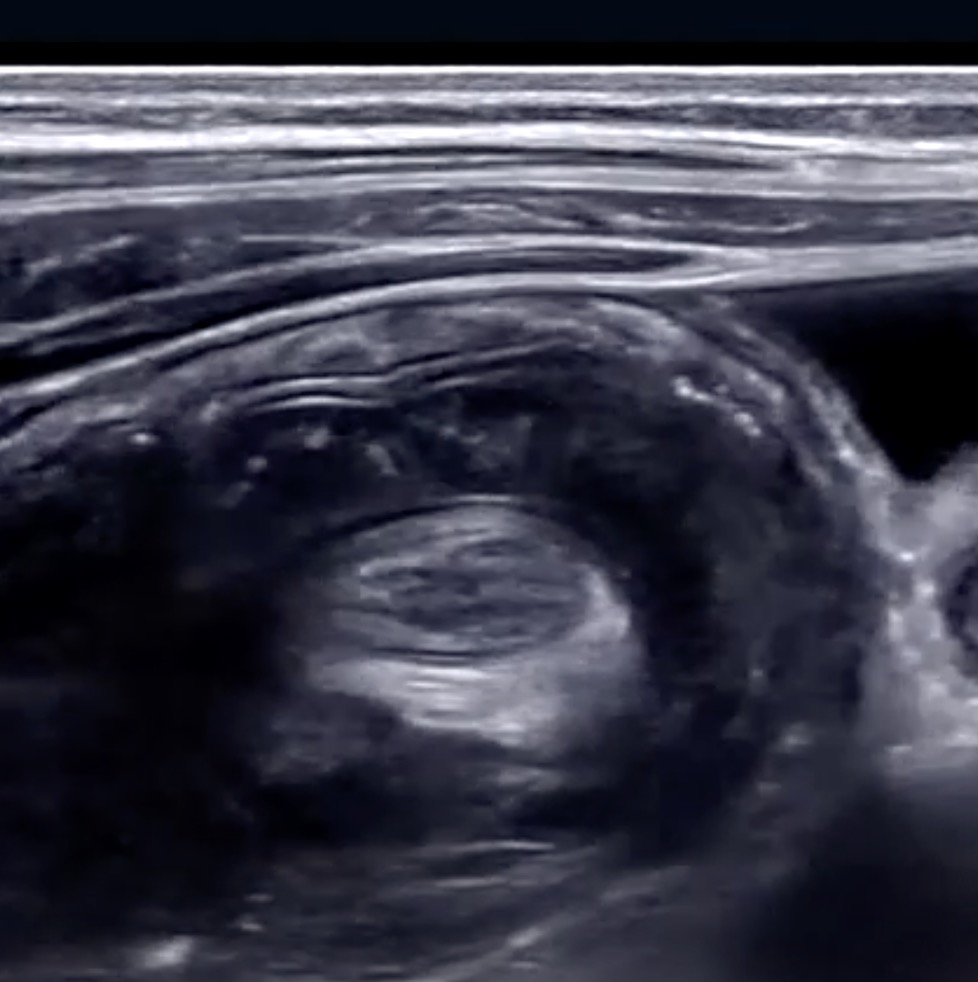

Conventional ultrasound systems link a fixed focus transmit with a dynamically focused receive. Due to

depth of field constraints, the transmit focus is typically weaker?than the receive focus resulting in poor depth penetration and the?need for multiple focal zones. For an ultrasound imaging system to

produce high quality images, the region of interest must be sufficiently sampled in both the axial and lateral dimensions to prevent several types of imaging artifacts. Dynamic Pixel Focusing permits utilization of the complete channel data set received from multiple, overlapping zones to retrospectively improve the position and focus of each individual data point. Using software algorithms to synthetically focus along every point in the receive beam effectively produces a round-trip beam focused at all depths, eliminating the need for multiple transmit foci. The image is 2-way focused at every point. A typical ZST+ ultrasound image has over 500 range samples, so the net effect is equivalent to a conventional beamformer-based system using 500-600 focal zones.